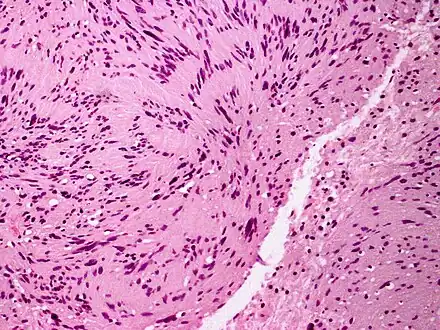

| Micrograph of a palisaded encapsulated neuroma | |

Palisaded encapsulated neuroma (PEN) is a rare, benign cutaneous condition characterized by small, firm, non-pigmented nodules or papules.[1][2] They typically occur as a solitary (single) lesion near the mucocutaneous junction of the skin of the face, although they can occur elsewhere on the body.[3]

As mentioned previously, PEN is a benign, firm, flesh-coloured lesion that typically occurs in dermis of the skin of the face. The lesions are typically between 2–6mm and are slow-growing.[3][4]

PEN is diagnosed by clinical recognition of the lesion and on subsequent histologic examination. Typically, the lesions are suspected to be schwannomas or neurofibromas clinically with PEN being an incidental finding on histology.[3]

PEN is typically diagnosed in patients between the ages of 40 and 60 years and occurs more frequently in females than males. The diagnosis of PEN may be difficult, even with confirmatory histology, due to its histological similarities with schwannomas and neurofibromas. It is imperative that the correct diagnosis is made the misdiagnosis of a neurofibroma may lead to unnecessary further investigation into associated systemic syndromes such as neurofibromatosis type 1 or multiple endocrine neoplasia syndrome.[3][4]